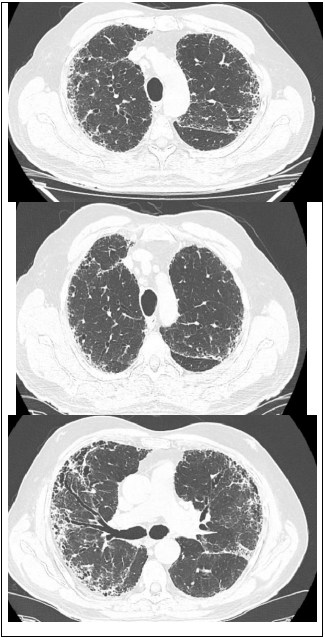

Leia o caso a seguir para responder às questões de 22 a 24.

Paciente 68 anos de idade, do sexo masculino, refere dispneia progressiva há 2 anos, inicialmente aos grandes esforços e atualmente aos pequenos esforços, associado com tosse seca frequente. Nega outros sintomas associados.

Ex-tabagista de 10 maços-ano, cessou o hábito há 20 anos.

Criou 2 pássaros em gaiola, em casa por 2 anos, cessou há 15 anos.

Trabalha em escritório de advocacia por toda a vida. Nega contato com mofo. Nega uso de medicações contínuas prévias ou atuais.

Ao exame em bom estado geral, leve dispneia, baqueteamento digital, IMC: 20, FR: 24irm, FC: 90 bpm, PA: 120x80mmHg, spO2 90% em ar ambiente. Ausculta pulmonar: estertores finos em velcro bibasais. Sem outras alterações.

Traz resultado de exame:

FAN negativo, FATOR REUMATÓIDE negativo

Espirometria: distúrbio ventilatório restrivo acentuado.

Tomografia de tórax: padrão típico de PIU (pneumopatia intersticial usual).

Enunciado 3206467-1

Qual é o tratamento indicado para esse paciente?

Enunciado 3206466-1

Qual é a melhor conduta para confirmar o diagnóstico desse paciente?

Enunciado 3206465-1

Qual é o diagnóstico mais provável para o paciente?